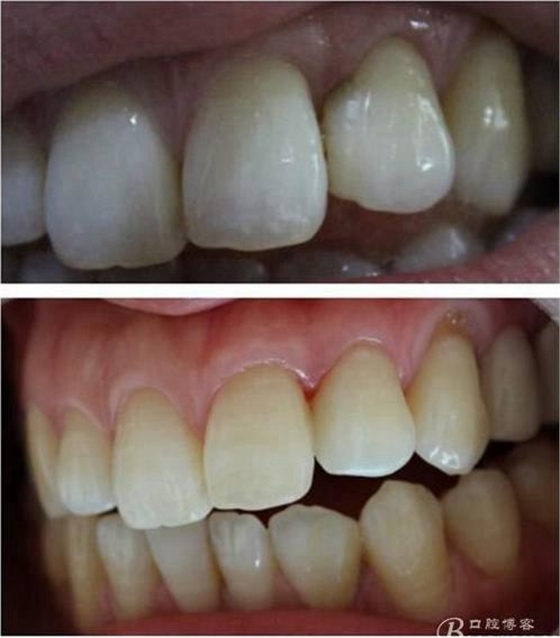

(這個(gè)是這個(gè)是學(xué)后第一次做美學(xué)修復(fù))

第一次做嵌體是樹脂嵌體。做完之后我跟我們主任炫耀,本來是想讓他夸我一下的。沒想到他說:“別高興太早,咱們時(shí)間上看。”說實(shí)話當(dāng)時(shí)心里一點(diǎn)底沒有,到底能用多長時(shí)間,自己一點(diǎn)沒底。